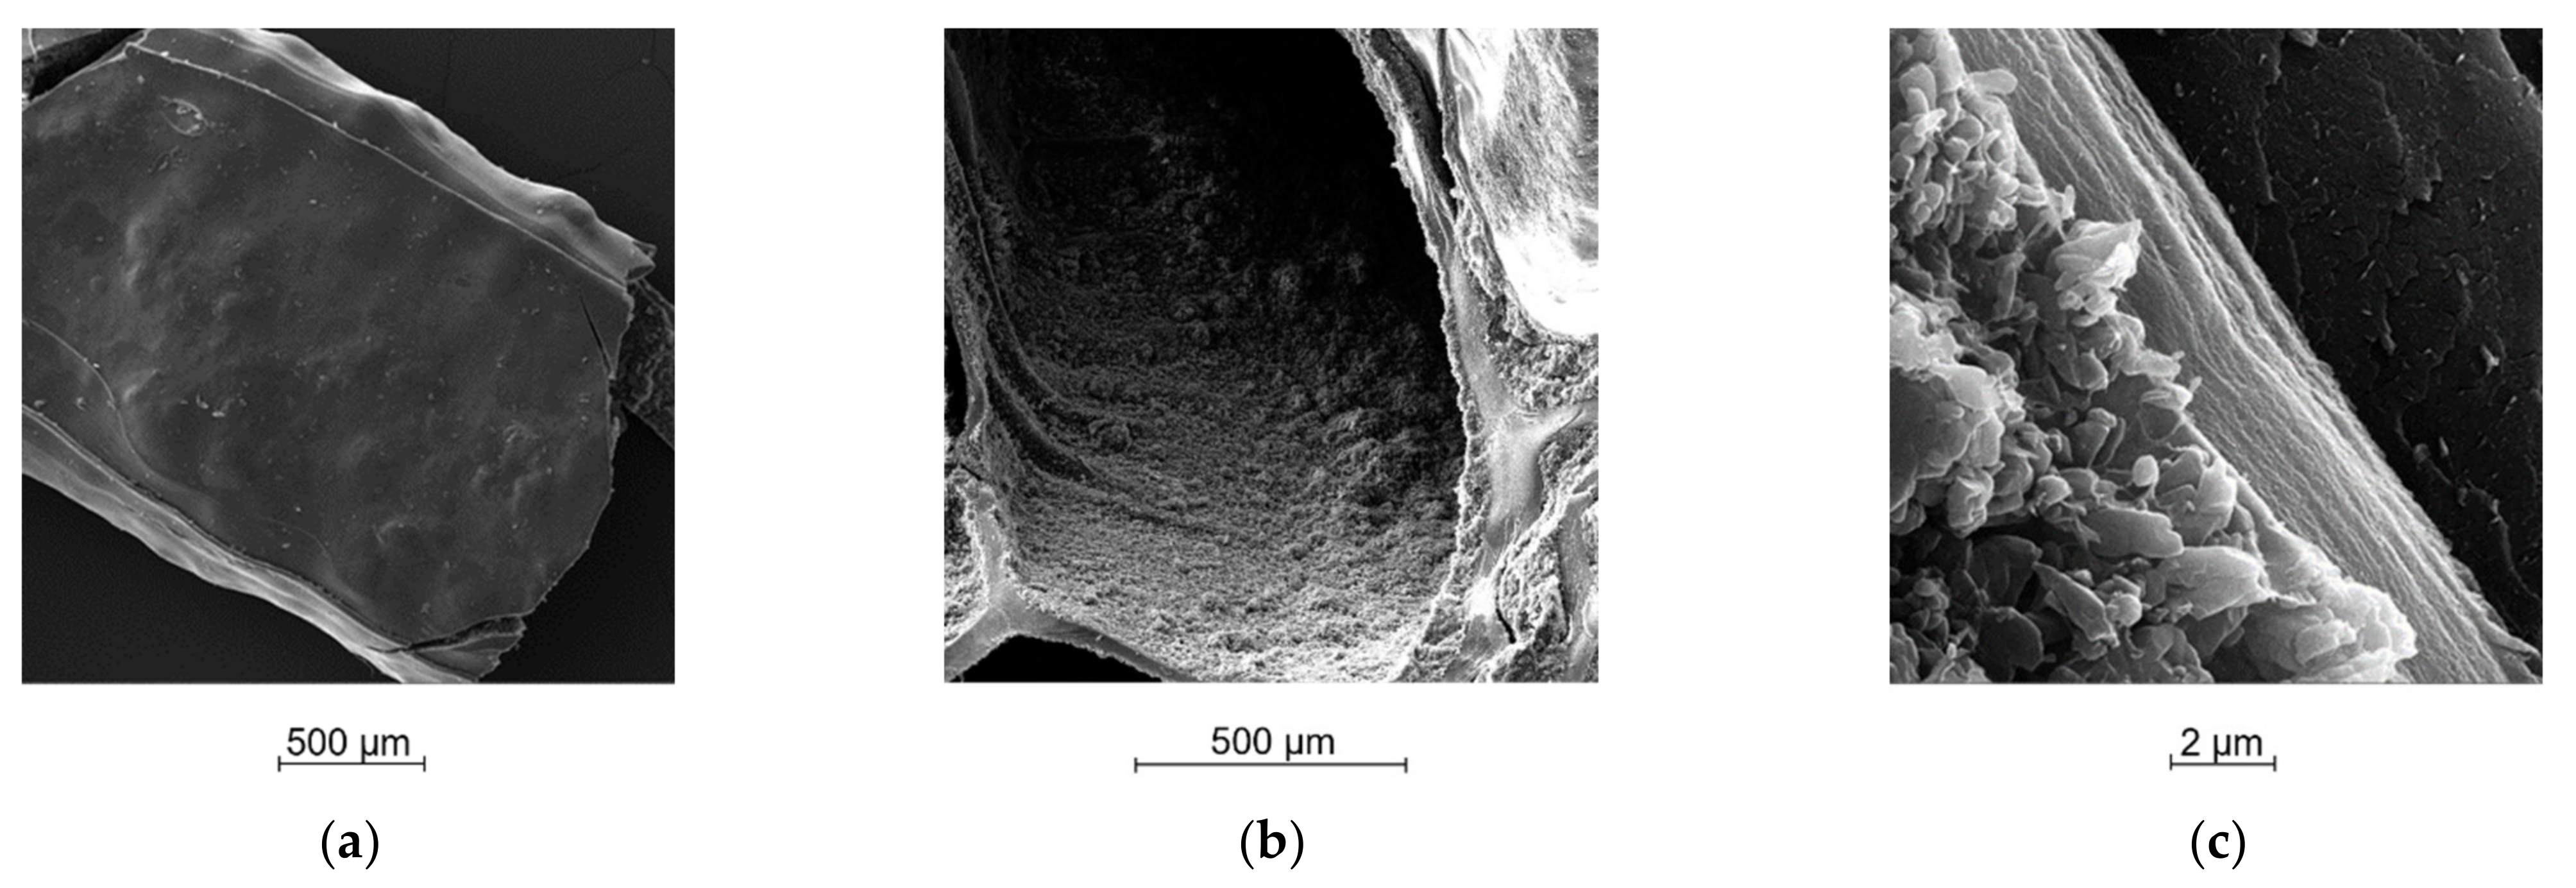

2.5. Morphological Analysis

4.2.6. Morphological Analysis